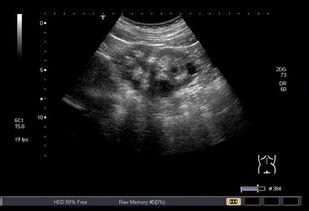

首先,得先给你科普一下什么是双肾B超。简单来说,双肾B超就是通过超声波来观察肾脏的一种检查方法。它可以帮助医生了解肾脏的大小、形态、位置以及内部结构,对于诊断肾脏疾病有着非常重要的作用。